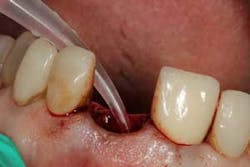

Although the literature varies as to the amount of bone volume that can be created/preserved, what material to use, as well as the indications for these procedures, (4) the majority of these studies agree that socket debridement is essential post-tooth extraction to ensure a good result. Socket debridement is particularly important when acute/chronic infections are present and cystic material lines the alveolar socket and/or tooth (figures 1 and 2). The complete removal of this infected tissue (figure 3) is tantamount to good bone fill, and can be the source of bone-graft contamination and infection.